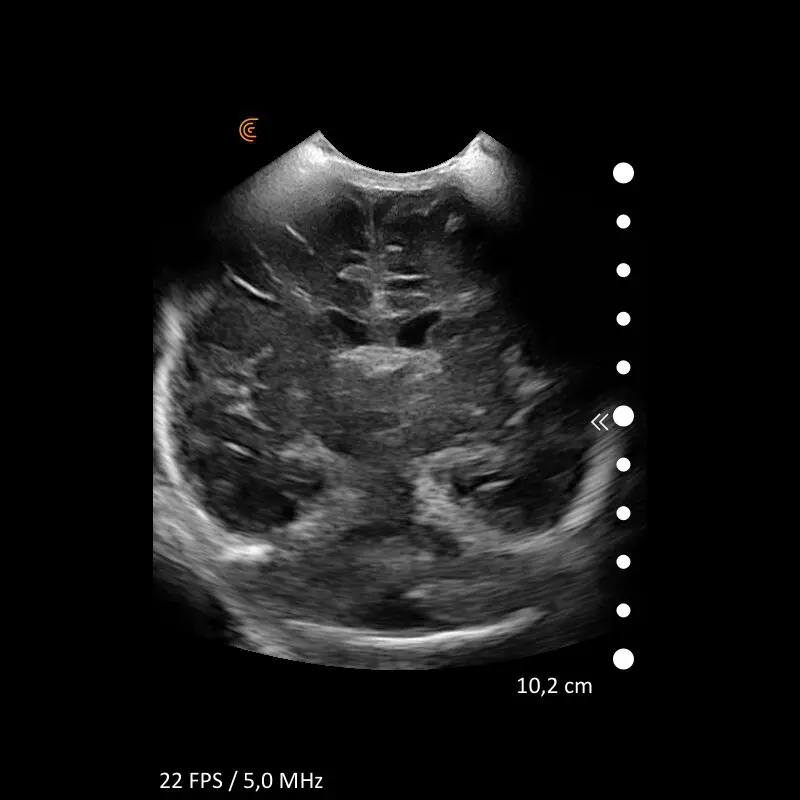

ProbeFix Dynamic is a new device that enables high-quality ultrasound measurements during dynamic exercise by keeping an ultrasound probe in place, allowing for muscle monitoring during intense movement and creating new research possibilities in muscle imaging.